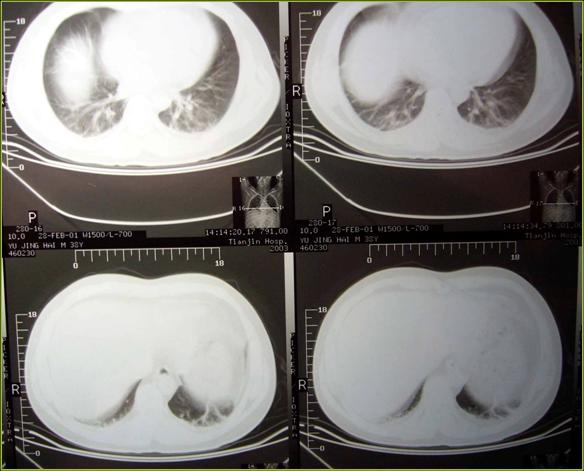

依患者临床表现,EKG表现以及经验临床考虑为肺栓塞,积极支持,抗凝治疗。平稳后进行CT检查提示:右肺下叶相当外基底段部位可见一尖端指向肺门,基底贴近胸膜之三角形,其尖端开口为细影线与肺门相连,余肺野清晰。确诊为肺栓塞。

考虑患者肺部栓塞部位及范围,以及术后不足24小时,存在出血可能,未给予RT-PA溶栓,积极吸氧,积极低分子肝素抗凝,解痉,扩容,监测凝血机能。复查D-二聚体依然阴性,FIB656mg/ml。三天后病情平稳,于2.21行双下肢多普勒检查,提示右股总静脉及股深静脉血栓,给予尿激酶治疗。3.2复查胸部CT,原肺部实变区域消失。随即复查双下肢多普勒依然可见血栓,复查左上臂X光片,固定愈合良好。3.21再次复查血栓再通,患者康复出院。